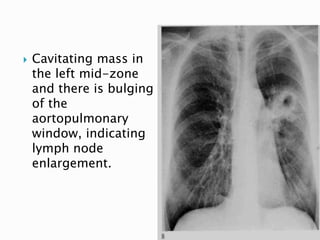

 Cavitating mass in

the left mid-zone

and there is bulging

of the

aortopulmonary

window, indicating

lymph node

enlargement.

44